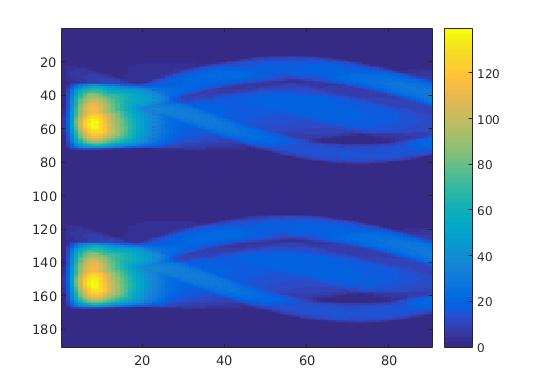

To simulate the synthesized SPECT data, we apply a Radon transform assuming a double detector gamma camera, which counts photons from two opposing projection angles per time step. For the more simple data set, we let the camera rotate clockwise around two degree per time step, in case of the complex data set we used modified projection angles, i.e. the camera alternatingly projects from an angle of i and 45+i degrees, in order to simplify the reconstruction. Each collimator consists of detector bins, so we obtain data points per time step and projection angle. The resulting sinogram data of the two underlying data sets are shown in figure 3.

In a first test, every image sequence was reconstructed out of the exact given sinograms. Additionally we tested noise corrupted data by first scaling the sinogram by a parameter , corrupting them with Poisson noise via the MATLAB imaging toolbox command imnoise and finally rescaling the image to the original range (see figure 4). The average count number per time step (i.e. the average of the discrete -norm of the data at each time step) is approximately in case of the heart-shaped data set and ca. in case of the rat liver simulation. The results at a certain number of time steps can be seen in figure 6 and 7. For comparison, we additionally performed a reconstruction with a simple alternating EM method, keeping the assumption that the tracer can be modelled as a sum of indicator functions and subconcentration curves, but neglecting any regularization terms. In all tests, the outer iteration number was set to 1000 with 10000 inner iterations per subproblem, to obtain a result within a reasonable time period. As stopping criterion, we chose the primal dual residual (cp. [12]) for the inner and the maximum over the Frobenius norms of and for the outer iterations. The results are displayed in 6 and 7 respectively.

As one can see in both figures, the reconstruction method applied to each data set performs very well, especially in contrast to the simple alternating EM method. This clearly shows the benefits of the proposed regularization methods. In case of noise-free given data, the shape of every object, where especially the heart is of higher interest, is clearly defined. As expected, we often observe errors in the edges of each region and where two regions are directly connected (the heart and the upper left circle). This causes the algorithm to incorrectly assign these pixels to another region. Furthermore, the reconstruction difficulties increase with an increase in noise. Some more pixels are assigned to the wrong region, which leads to a small hole-like structure within the heart region and causes a slight blurring effect. In the second data set the method clearly outperforms several other approaches by providing very clearly defined regions and even reconstructing fine structures of the phantom. However, as mentioned before, a clear reconstruction of the rat liver required highly optimized parameter sets, which makes the whole problem quite susceptible to parameter changes.